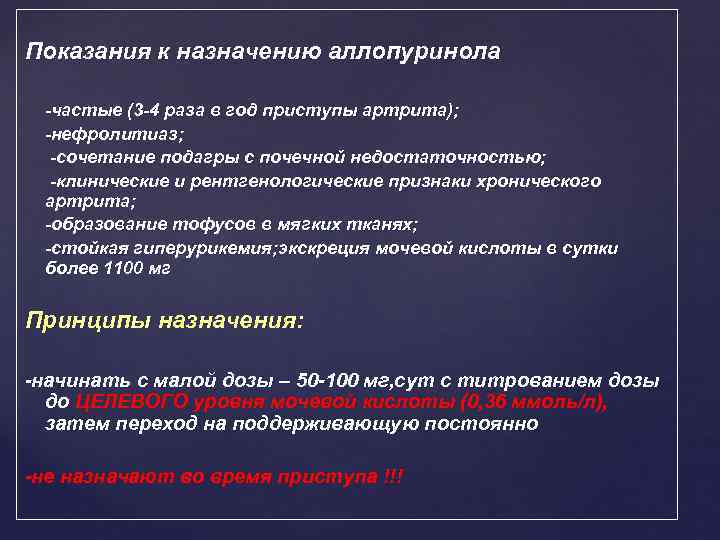

Показания к назначению аллопуринола -частые (3 -4 раза в год приступы артрита); -нефролитиаз; -сочетание подагры с почечной недостаточностью; -клинические и рентгенологические признаки хронического артрита; -образование тофусов в мягких тканях; -стойкая гиперурикемия; экскреция мочевой кислоты в сутки более 1100 мг Принципы назначения: -начинать с малой дозы – 50 -100 мг, сут с титрованием дозы до ЦЕЛЕВОГО уровня мочевой кислоты (0, 36 ммоль/л), затем переход на поддерживающую постоянно -не назначают во время приступа !!!

Показания к назначению аллопуринола -частые (3 -4 раза в год приступы артрита); -нефролитиаз; -сочетание подагры с почечной недостаточностью; -клинические и рентгенологические признаки хронического артрита; -образование тофусов в мягких тканях; -стойкая гиперурикемия; экскреция мочевой кислоты в сутки более 1100 мг Принципы назначения: -начинать с малой дозы – 50 -100 мг, сут с титрованием дозы до ЦЕЛЕВОГО уровня мочевой кислоты (0, 36 ммоль/л), затем переход на поддерживающую постоянно -не назначают во время приступа !!!